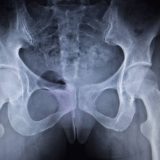

良い姿勢とよくいわれますが、股関節に痛みを抱える方にとって、良い姿勢とはどのような姿勢なのでしょうか。

股関節に限らず、膝関節や腰に痛みを抱える方は姿勢や歩行について考えるのはとてお良いことだと思います。というよりも、姿勢や歩行をしっかり考えないと痛みや症状を根本的に解決することができません。